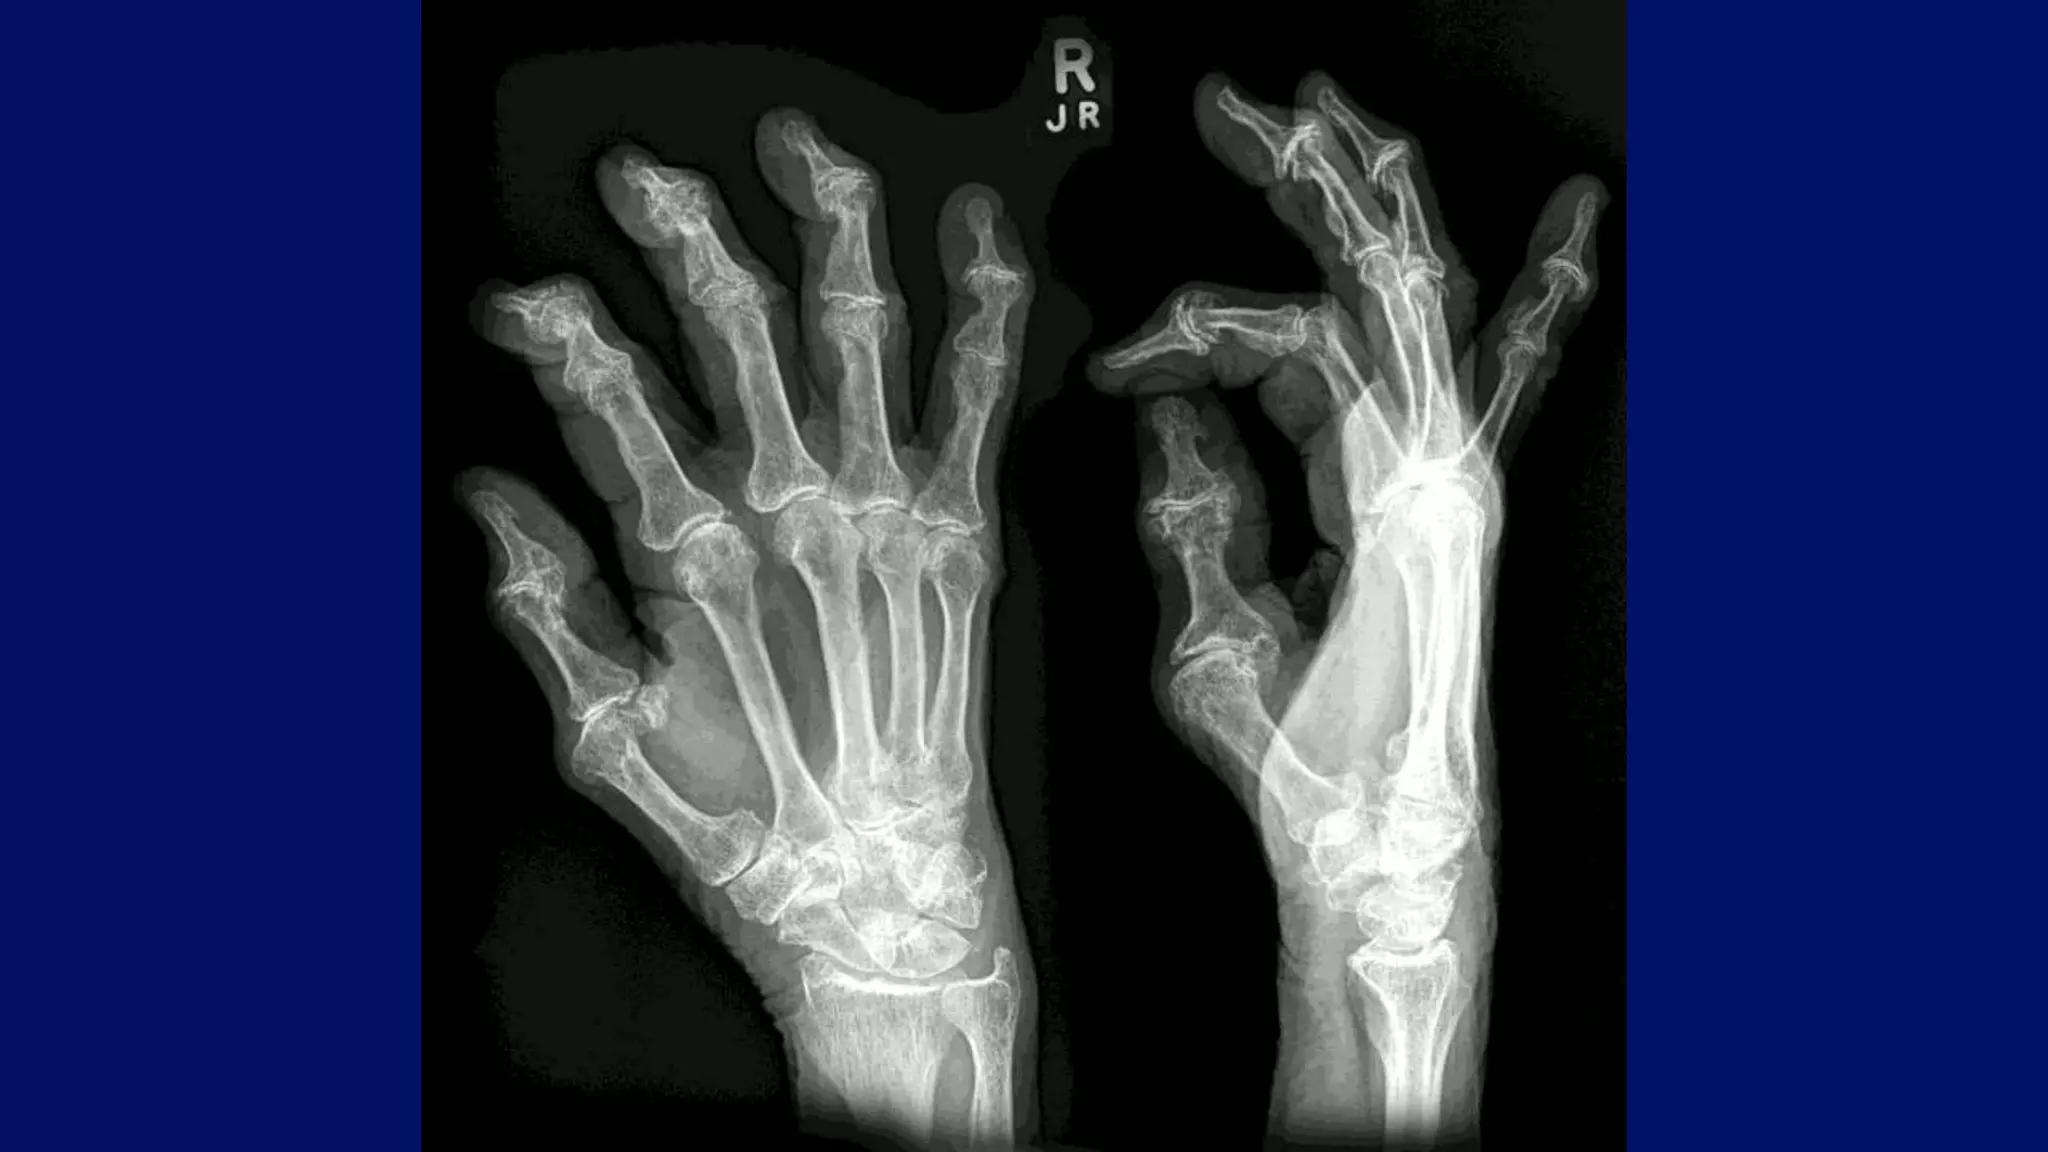

Arthritis or not

Normal DJD